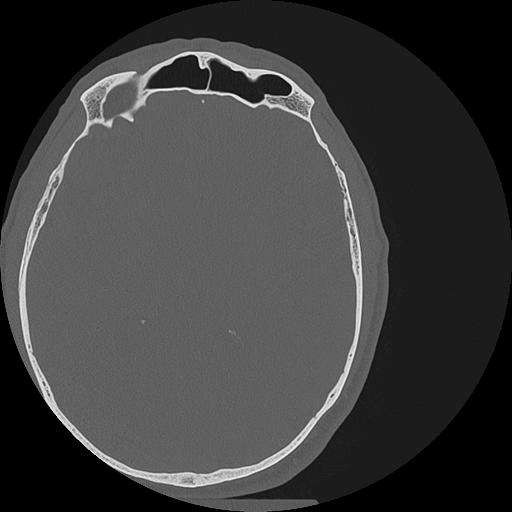

7 HUESO,,Vol,0.5,HUESO,,